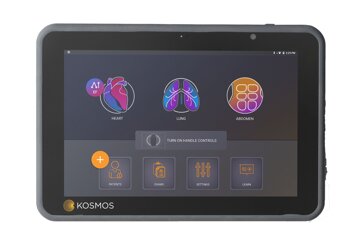

Kosmos

Zbulo teknologjinë e avancuar të ekografit palmare Kosmos nga EchoNous! Imazhe 2D të cilësisë më të lartë dhe modulet operacionale si PW, TDI dhe CW Doppler

Tablet Compatibili

The Bridge

Tablet mjekësor i pronarit të cilësisë së lartë. I certifikuar për rëniet nga 1m lartësi